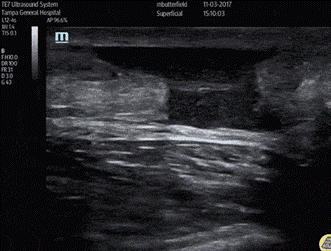

X-rays usually do not identify any osseous pathology, although avulsion fractures can occur. However, on closer examination, soft tissue swelling and changes in the Achilles shadow are often evident. In the ED, ultrasound is the best confirmatory test. Using the linear probe, the Achilles tendon is best evaluated in longitudinal view, evaluating for tissue gaps, disorganized fibers, fluid, or hypoechogenicity (see Figure 2).

Figure 2 - Tissue gap, fluid, and disorganized muscle fibers seen in longitudinal view of the Achilles